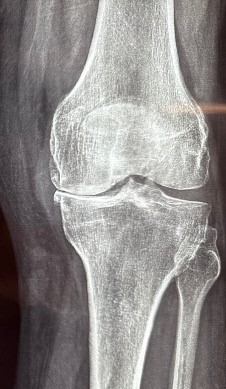

Η οστεοαρθρίτιδα είναι η συχνότερη αιτία για την οποία γίνονται οι αρθροπλαστικές στο γόνατο.

Η άρθρωση αποδιοργανώνεται, ο χόνδρος που καλύπτει τις αρθρικές επιφάνειες καταστρέφεται και εγκαθίσταται προοδευτικά επιδεινούμενος πόνος και δυσκαμψία της άρθρωσης.

Μία απλή ακτινογραφία επιβεβαιώνει την διάγνωση και την έκταση της βλάβης.